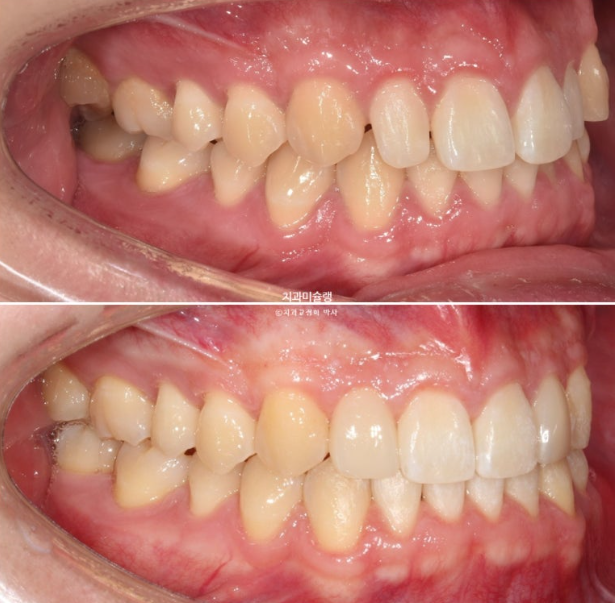

오늘은 가위교합, 중심선 이슈, 거미스마일 등등에 왜소치까지 있는 복잡한 케이스를 인비절라인으로 어떻게 치료하는 지 보여드리겠습니다.

2022년 10월 비대칭으로 내원하신 분입니다.

중심선 불일치, 왜소치로 인한 벌어짐, 송곳니 덧니 등이 보입니다.

이 환자분이 한쪽으로만 씹었던 이유는 반대쪽에 가위교합이 있었기 때문입니다.

파란 화살표가 가위교합이고 위 큰어금니는 바깥으로 나가있고 대합치는 안쪽으로 쓰러지며 가위처럼 서로 엇갈려 교합되는 상태를 말합니다.

파란 화살표 치아가 바깥으로 뻗치면서 가위교합의 원인이 됩니다.

2022년 10월부터 24년 4월까지 1년반동안 첫세트 장치를 모두 낀 후 모습입니다.

24.04

가위교합은 해결이 되었지만 아직 어금니 교합이 긴밀하지 않습니다.

배열은 완벽합니다.